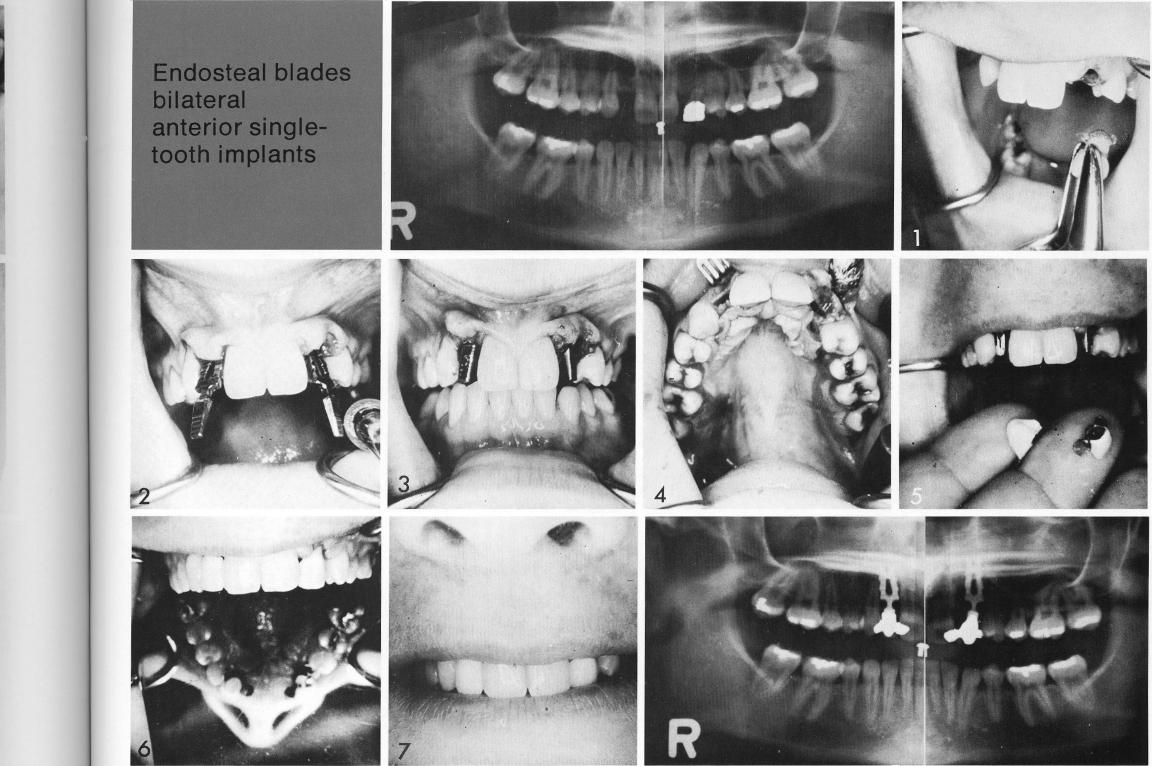

a The young patient with both a lateral incisor and a cuspid missing bilaterally (1), had space for only a single replacement (2). Because the neighboring teeth were healthy, stable, and attractive, it was possible to plan single-tooth replacements supported by single-tooth bladevents (3,4). These were cemented over the bladevents (5,6) to provide handsome replacements without the use of a bulky removable appliance or sacrificing neighboring teeth for inclusion in another type of fixed restoration.

1 The patient with space for only a single maxillary tooth replacement